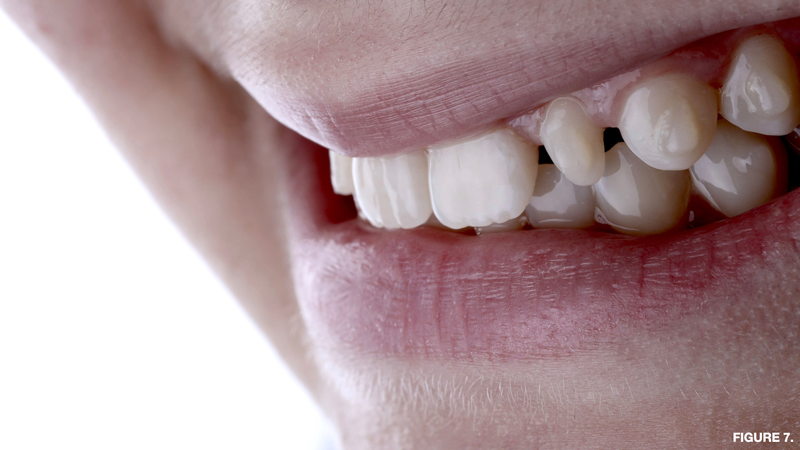

A common concern for patients who utilize teeth-bleaching products during aligner treatment is the potential for discoloration or yellowing of the tooth structure under the adhesively bonded component that was not in contact with the bleaching agent.25 However, numerous studies, as well as the author's own clinical experience, have demonstrated that the permeability of the dental hard tissues and the capillary action of peroxides allows complete penetration and diffusion of the bleaching medium under any existing resin buttons, brackets, or composite restorations (Figure 7 through Figure 9).26,27

Fig 7. Initial

presentation before teeth-bleaching treatment (left panel) and pretreatment tooth shade evaluation (right panel) of a patient with stained

composite resin on gingival third of maxillary central incisors.

Figure 7